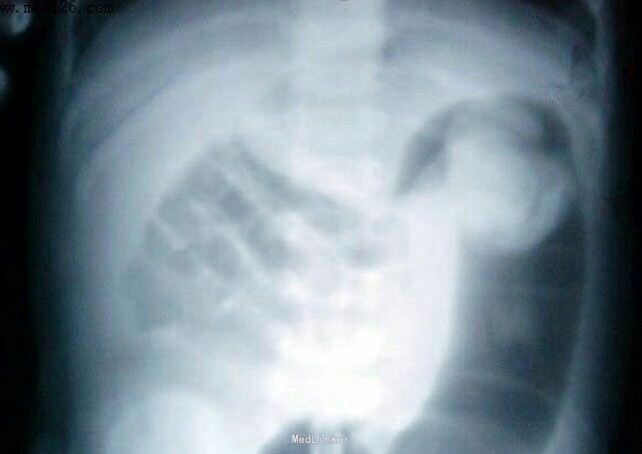

患儿男,7岁。因“间断性腹痛4天,肛门停止排气1天”入院。查体:腹软,左侧腹部局部压痛,无反跳痛,未扪及包块,未见胃肠型及蠕动波。 血生化、肝肾功能及肿瘤指标均在正常范围。腹部CT检查示:降结肠内见突入腔内的软组织块影,直径约3cm。肠镜示:降结肠近脾曲处见突入腔内的肿块影,直径约3cm,考虑为结肠癌。镜下取适量组织行病理检查,结果提示为少量纤维、脂肪组织,其间见少量淋巴细胞浸润。入院后行剖腹探查,术中降结肠脾曲见肿块,直径约4cm,术中诊断为降结肠癌,行根治性左半结肠切除术。病理结果:降结肠弥散性大B细胞淋巴瘤。镜下肿瘤细胞弥散排列、体积较小、较规则、胞质少、核深染、核分裂相偶见,免疫组织化学CD20+,Ki-67增殖指数约90%。 诊断为:淋巴瘤。术后患者行CHOP方案(环磷酰胺+多柔比星+长春新碱+泼尼松)化疗2次,间隔1个月,目前随访9个月无异常。